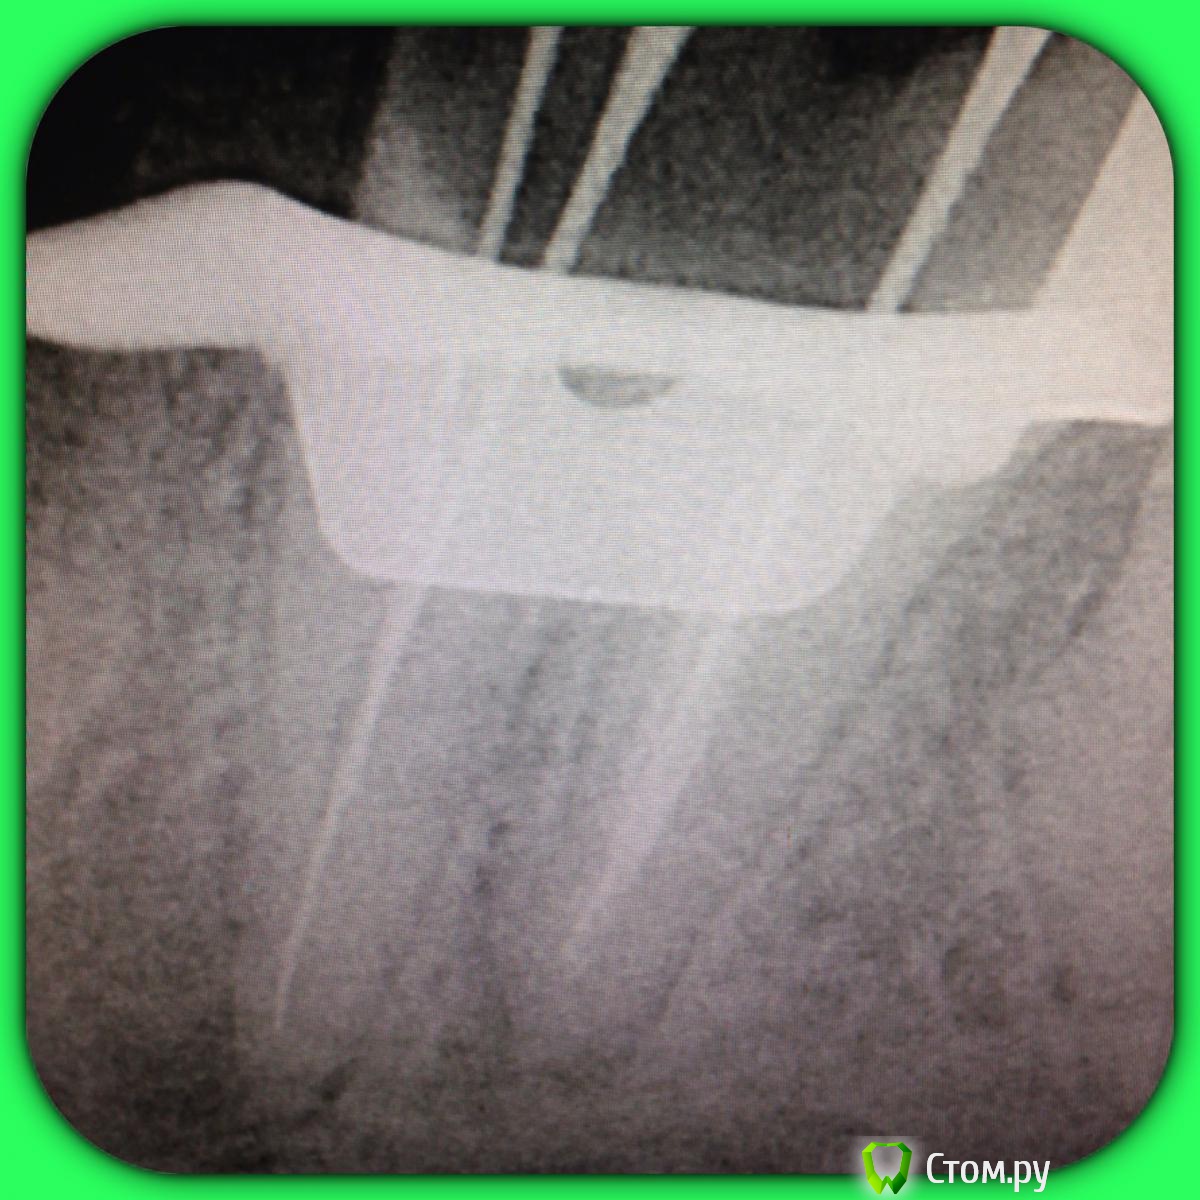

SSTi Опубликовано 13 июня, 2014 Автор Поделиться Опубликовано 13 июня, 2014 37. Медиальная стенка разрушена. Огромная старая пломба. Из жалоб только иногда болезненность по переходной. Редко. Очень. Делаю снимок. Коффер, преп, в дистальном какая-то паста плотная очень, светло-молочного цвета. В медиальный язычный без проблем попал. Щечный пришлось ковырять. Теперь о неприятном. Дистальный распломбировал, прошел, при этом раскрутил 3 протейпера и 1 профайл. В язычном медиальном проблем не было. А вот щечный- жутко узкий, прошел до куда смог. Раскрутил 3 протейпера, 2 профайла, 1 pathfile.... Дальше никак. До апекса еще миллиметров 5 точно. Хорошо хоть без поломок. Ручные к файлы гнулись только так. Даже десятка не идет. В общем очень хорошо помыл и кальций. Не знаю , что с щечным делать??? Биться дальше?? Сомневаюсь, что смогу. Это в процессе. Вот до куда дошел в щечном. С дистального потом убрал со стенок остатки материала Ссылка на комментарий

Чертков Александр Опубликовано 13 июня, 2014 Поделиться Опубликовано 13 июня, 2014 http://s019.radikal.ru/i626/1406/86/f21a182f0beb.jpgА по моему апекс здесь.... Ссылка на комментарий

SSTi Опубликовано 13 июня, 2014 Автор Поделиться Опубликовано 13 июня, 2014 У язычного длина 23.5. В щечный файл заходит на 17-18мм. Надо будет развернуть трубку и сделать под углом в следующий раз. Апекс молчит как партизан в щечном. Ссылка на комментарий

SSTi Опубликовано 13 июня, 2014 Автор Поделиться Опубликовано 13 июня, 2014 А чего он должен показывать на такой глубине?)Хотя бы то, что я двигаюсь по каналу к апексу. На новапексе же есть такая фишка. Так где думаете апекс тут??? Ссылка на комментарий